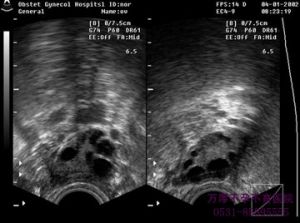

2、陰道探頭塗耦合劑,套消毒橡膠套,固定穿刺架。

3、選擇囊腫顯示最清楚、距離陰道探頭最近、避開盆腔大血管及子宮的部位作為穿刺點,囑患者屏氣,將穿刺針放入穿刺架後沿超聲引導線快速刺入囊腫內,使針尖停留在囊腫內後1/3~1/2,拔出針芯,抽吸囊液。即將抽淨囊液時應注意觀察針尖的位置,儘量靠近囊腫後壁。根據囊腫情況決定是否注入無水乙醇保留。囊液根據情況送常規、生化、細菌培養、病理檢查。